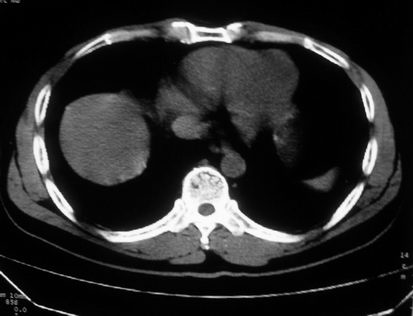

男,体查发现右肝低密度,右肾高密度结节影。高密度ct值92hu,囊肿?

肝右叶囊肿或血管瘤?右肾高密度囊肿。建议增强。

肝右叶圆形低密度灶,考虑囊肿或血管瘤,建议ct增强检查;右肾包膜下高密度圆形灶,考虑:囊肿并出血